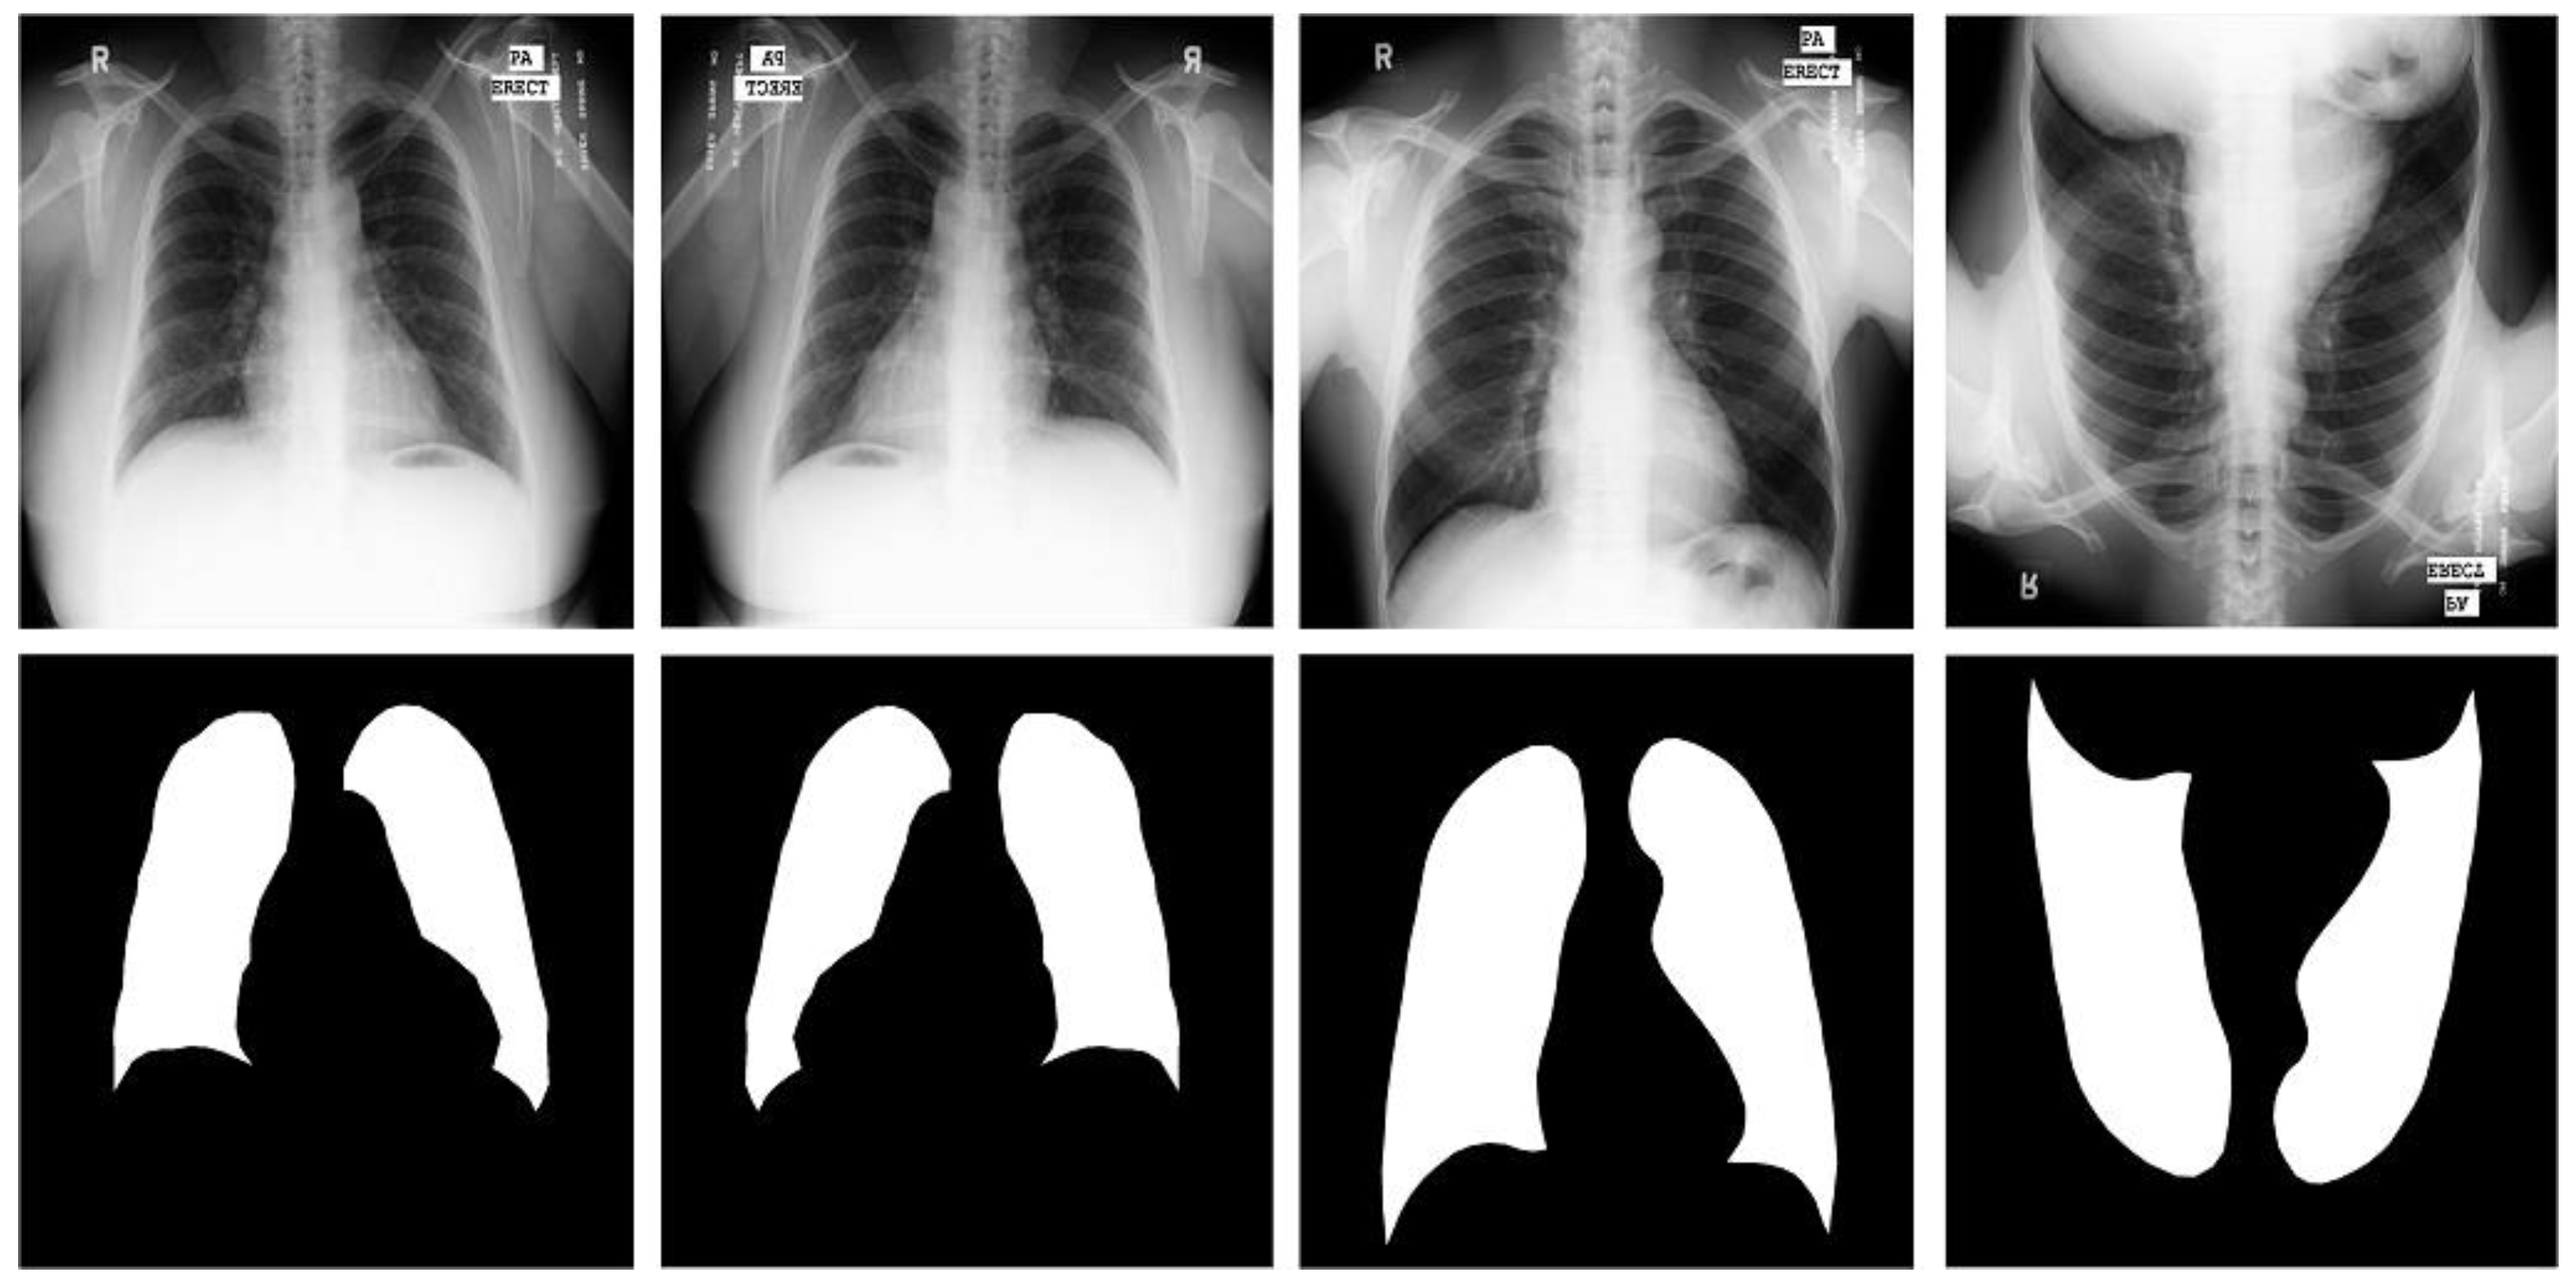

Shenzhen dataset [18]. This dataset is a collaboration between the Third People’s Hospital of Shenzhen, Guangdong, China, and the National Library of Medicine of Maryland, USA. It contains 662 radiographic images of the human chest region; each CXR radiograph is a single-channel grayscale image with a color depth of 8 and an average resolution of 326 radiographs healthy subjects and 336 from patients with tuberculosis. We used this dataset supervised and labeled by professional radiologists, which was provided by Jaeger et al. [18]. For the Shenzhen dataset, we used simple three-fold machine rotations and a simple three-fold flip data enhancement strategy, and trained the original image data together in the expanded dataset, which was expanded to seven times the original size, containing 4634 images. We use 3710 images as training cases, 336 images as validation cases, and 336 images as test cases. Table 1 shows the CXR and its specification summary of the X-ray film images of the three data sets after data enhancement, and the original and enhanced example images of the three data sets are shown in Figure 3, Figure 4 and Figure 5.

Figure 4.

Images and masks of the MC dataset.